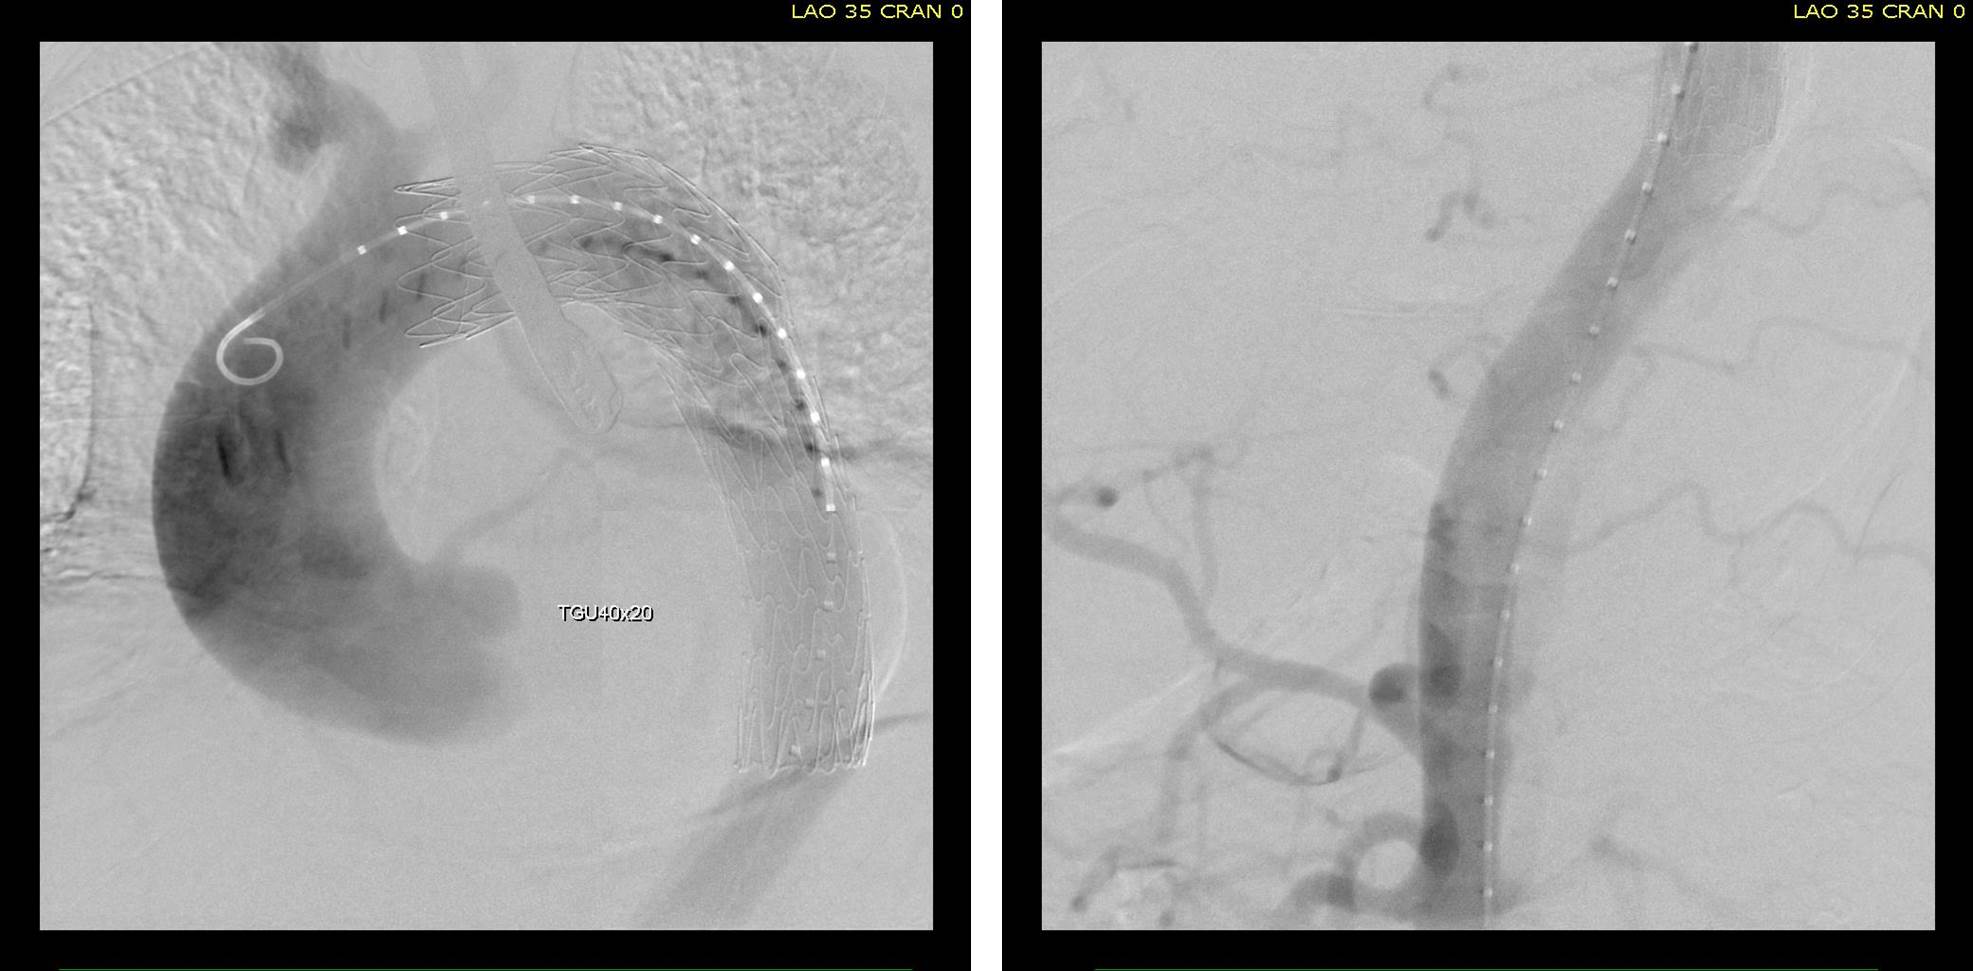

As seen below, the graft excluded the celiac and SMA. Late in the phase of the final aortogram (second panel) there was an endoleak that persisteed despite multiple ballooning. The timing suggested the intercostals and phrenic vessels contributed to a type II endoleak, but it was concerning.

The bypasses were sent from the infrarenal aorta to the common hepatic artery and the SMA close to its origin, and the origins of the celiac axis and SMA were clipped. The bypasses were then done with a 10x8mm bifurcate Dacron graft originally for axillofemoral bypassing. It had spiral rings which I removed at the anastomosis and this resulted in a kink at the closer bypass. Usually, I loop this for iliomesenteric bypass but there was not enough distance from the infrarenal aorta. I have to add a little trick I modified from my pediatric surgery experience as a resident -a Heinecke-Mikulwicz graftoplasty:

This worked to relieve the kink as evidenced on the aortogram above. After closing the laparotomy, I placed a chest tube in the right chest. The patient had a course prolonged by a classic systemic inflammatory response syndrome, with fevers, chills, and leukocytosis. He bled for a while but stopped with correction of his coagulopathy. All blood cultures were negative, but a CT scan was performed out of concern for the endoleak, and the possibility of continued bleeding.